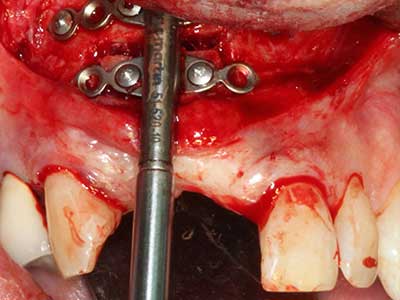

Както е показано в миналото, всяка костна хирургия представлява възможна индикация за пиезохирургия. По този начин, за препарацията на подвижни сегменти в остеогенеза (Фиг. 23-25) и остеотомия се използват специални накрайници, без да се застрашава снабдяването с кръв в кресталната зона, което е от съществено значение за успеха и на двете техники (Gonzalez-Garcia, Diniz-Freitas et al. 2008).

Чисто ортодонтските индикации включват ортогнатна хирургия, генопластика (Фиг. 27-30) и орбитална декомпресия при пациенти с напреднала ендокринна орбитопатия, в резултат от Базедова болест (Ponto, Zwiener et al. 2014). Пиезо апаратите се използват също за лицево-челюстна хирургия и за отстраняване на тумори в основата на черепа в различни болници.